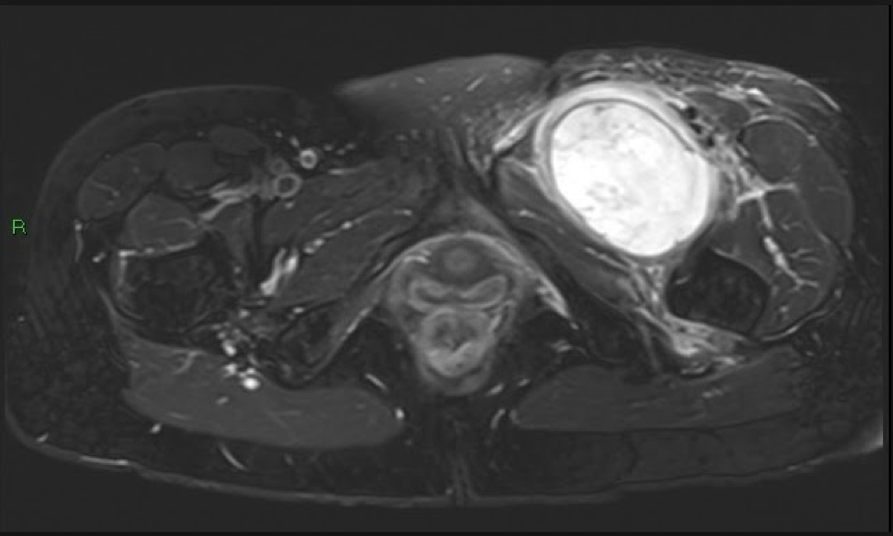

Fig.06. MRI Pelvis with T2-weighted PD fat-suppressed sequences again shows a large, heterogenous intermuscular mass in the medial compartment of the left upper thigh with associated mass effect and perilesional oedema.

Learning Point 3: While ultrasound is valuable for evaluating suspicious features of soft tissue lesions, gadolinium-enhanced MRI remains the gold standard for evaluating tumour extent and infiltrative spread. The tail sign of fascial spread was demonstrated in this case and is a key diagnostic sign, before formal histopathology confirmation (Figure 4-7).